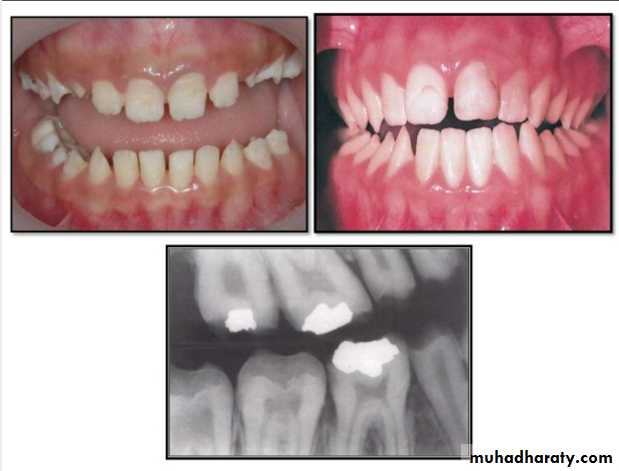

Hypoplastic Amelogenesis Imperfecta:

* Due to some defect in ameloblasts enamel fails to develop to its normal thickness dentin exposed the tooth shows yellowish-brown color.*Enamel is randomly:

pitted .

rough OR smooth &glossy.

*The occlusal surfaces of the posterior teeth are relatively

flat with low cusps due to attrition of cusp tips that were initially low and not fully formed. An anterior open bite may be noted. defects become stained but teeth are not especially susceptible to caries unless enamel is scanty and easily damaged.

Generalized hypoplastic type

Amelogenesis ImperfectaAffects primary &permenant dentition

Severe mottling of the enamel surface.

Hypomaturation Amelogenesis Imperfecta:

*Enamel is normal in form on eruption but:

opaque.white to brownish-yellow.

softer than normal.

tends to chip from underlying dentin.

Radiographically:

Affected enamel exhibits radiodensity similar to dentin.